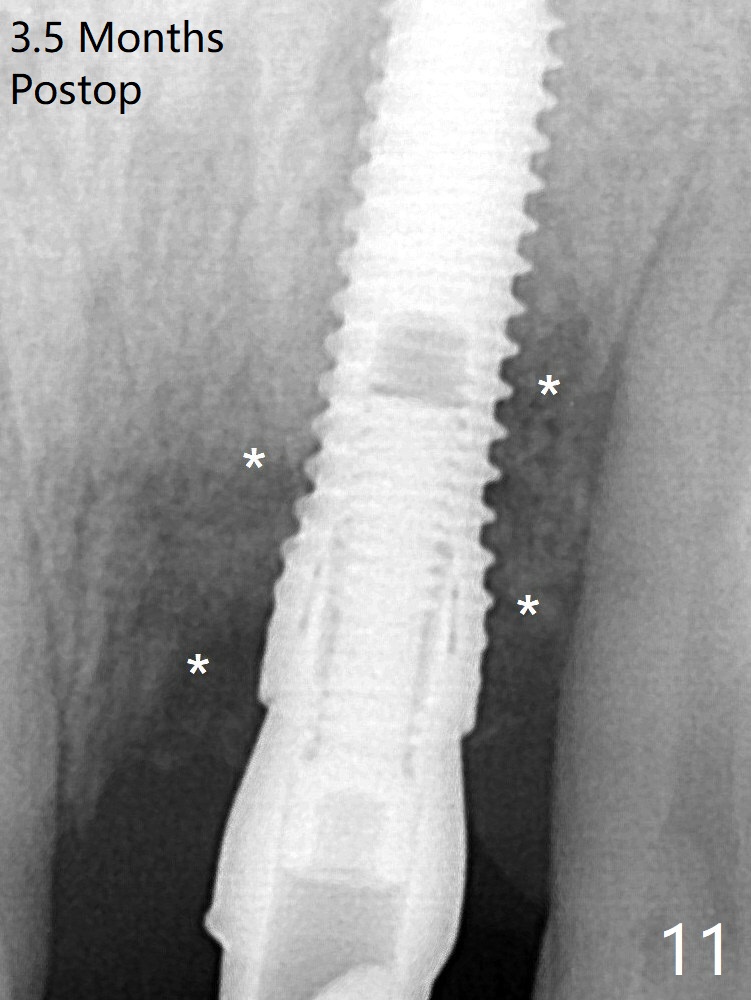

After placement of a 3.8x15 mm implant, PRF is laid against the inner surface of the buccal defect and allograft (Fig.5 *) is packed mainly in the buccal gap before and after insertion of a 4.5x5(4) mm abutment. The bone graft remains in place 3.5 and 4.5 months postop (Fig.11,12 *). Between 3 and 4 months postop, the mesial surface of the abutment has been trimmed (Fig.12 >). Since the mesial surface of the tooth #10 will be reduced (white curved line) to correct the upper dental midline, an angled abutment (red line) seems to be necessary to shift the provisional distal. The socket at UL1 seems to have healed except the most coronal 1 year 3 months postop (Fig.14 *).